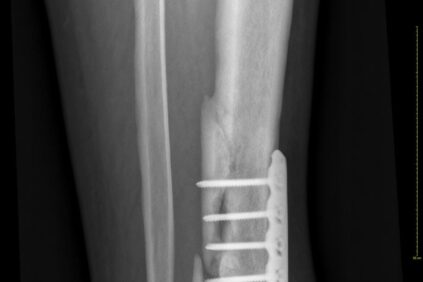

Contamos con la superespecialización de un equipo que se dedica de forma exclusiva a tratar patologías que afectan a mano y muñeca. Dicha superespecialización requiere de conocimientos y experiencia en cirugía ortopédica, plástica, vascular y neurocirugía.

Nuestros servicios en Cirugía de la Mano y Microcirugía.

Abarcamos todas las intervenciones de muñeca, mano y aquellas que requieran microcirugía.

- SuperespecializaciónEn cuestión del órgano vital de la mano

Equipo con amplia experiencia en reconstrucción de extremidades.